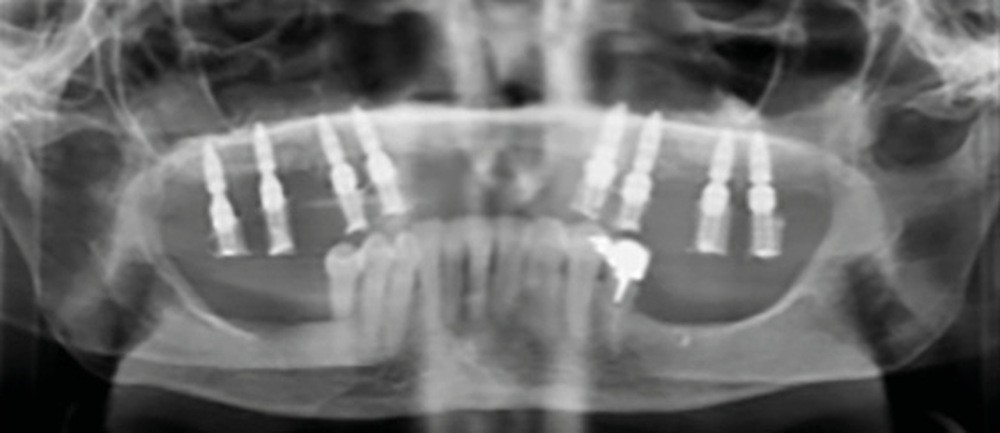

Une patiente de 62 ans, non fumeuse Asa1, porteuse d’une prothèse amovible partielle (PAP) mandibulaire et maxillaire, souhaite bénéficier d’une solution fixée. Il persiste au maxillaire 13, 23, 14 et 24, associées à une forte résorption type FP3 [1, 2] (fig. 1).

Le matching classique avec les fichiers STL et Dicom fut imprécis. La technique inspirée du « double scan » à l’aide de points radio-opaques sur la PAP provisoire maxillaire et d’un double CBCT a permis d’obtenir un matching extrêmement précis et la conception d’un projet prothétique numérique (Nemotec) associé à un Smile design (fig. 2). La modélisation 3D et le CBCT ont permis d’élaborer une planification implantaire, des guides à étages et un bridge complet provisoire en PMMA usiné (Biotech). La planification de 8 implants au niveau des 7/6/4/3 en fonction du volume osseux disponible et du projet prothétique virtuel a confirmé la possibilité de proposer un traitement sans greffe antérieure (fig. 3).